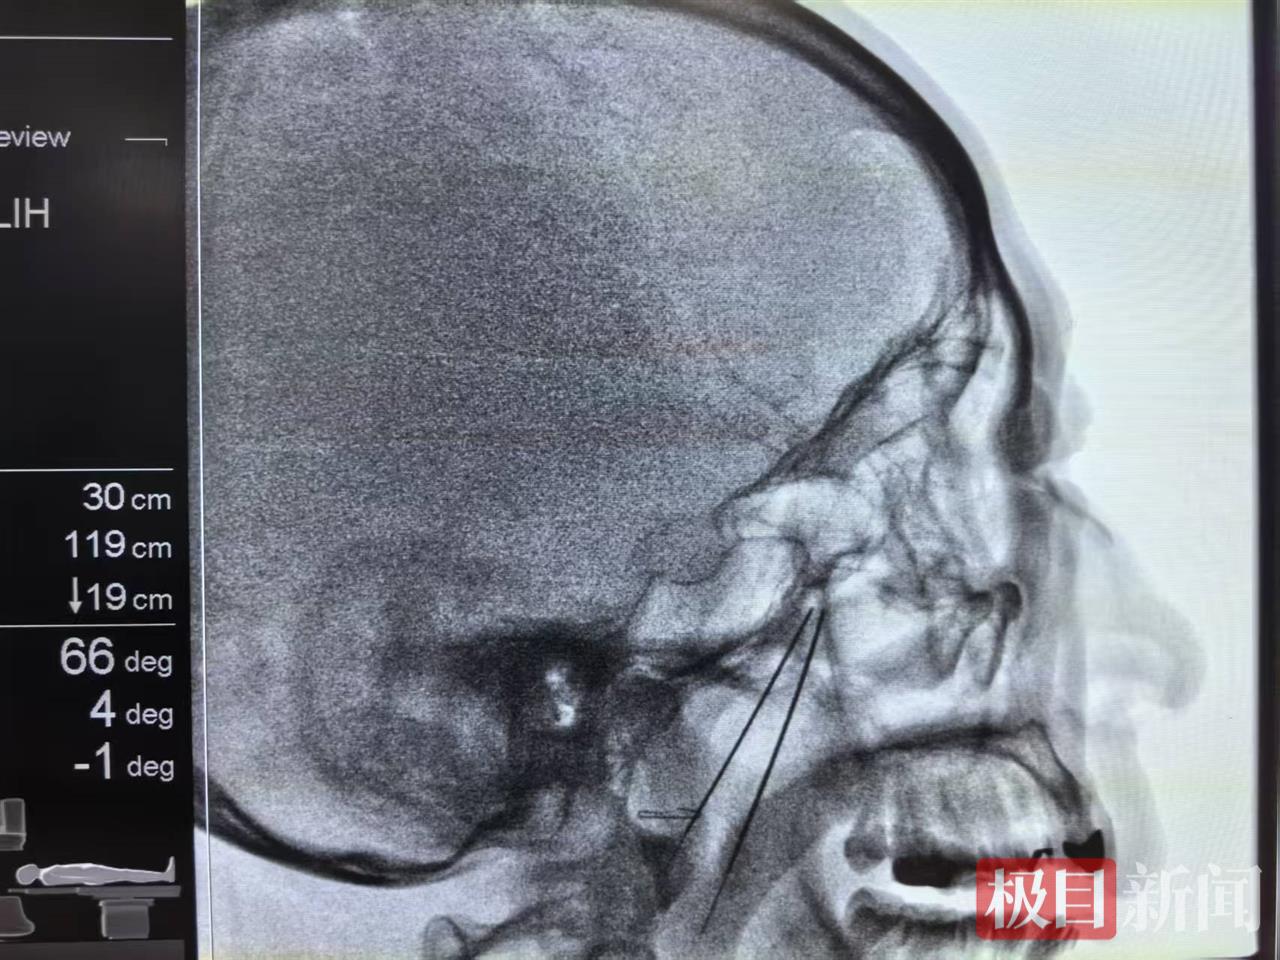

术中,贾一帆在影像学精准引导下,用一根穿刺针成功定位目标神经节——蝶腭神经节,并通过温和的脉冲电流对其进行调控。整个微创手术过程约15分钟。术后,张先生感觉症状缓解,术后面部无创口,观察一小时后即安全回家。近一年随访证实,其鼻炎症状基本未再复发。

科学研究证实,蝶腭神经节是调节鼻腔血管和腺体的“总开关”。贾一帆介绍,脉冲射频调控术是在影像精准导航下,利用42℃以下的温和电流作用于该神经节,可有效提高交感神经兴奋性,调节神经肽释放,从而纠正紊乱的鼻黏膜生理功能,显著改善鼻塞、流涕等核心症状。